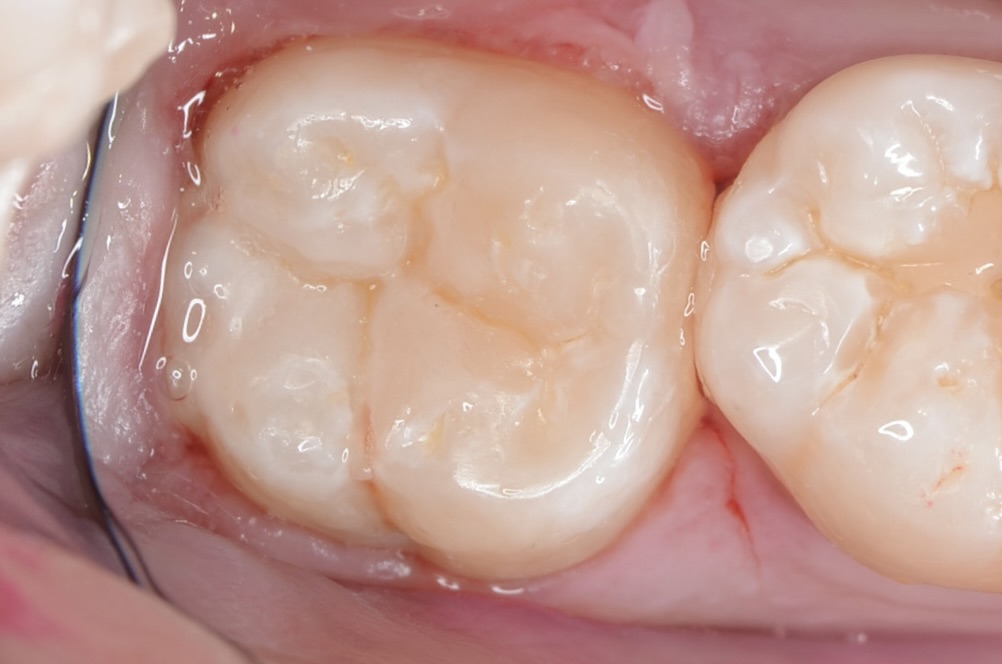

神経を取りたくない・MTAセメント・歯髄保存療法虫歯の治療・ダイレクトボンディング

30代 虫歯治療 VPT(歯髄温存療法)ダイレクトボンディング #66

01歯髄保存治療

歯髄保存治療は、歯の神経をできるだけ残し、自然の歯を保つことを目指す治療法です。虫歯などによる歯の痛みを軽減し、歯の寿命を延ばします。